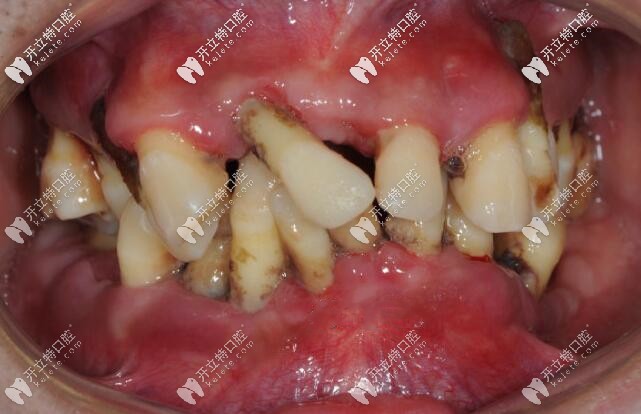

我覺得自己全口牙好似都活動了,就吃面條都不太能咬動,后來到醫(yī)院醫(yī)生建議得治是重度牙周炎,醫(yī)生建議把牙齒全部拔掉。

35歲重度牙周炎顧客的牙齒情況